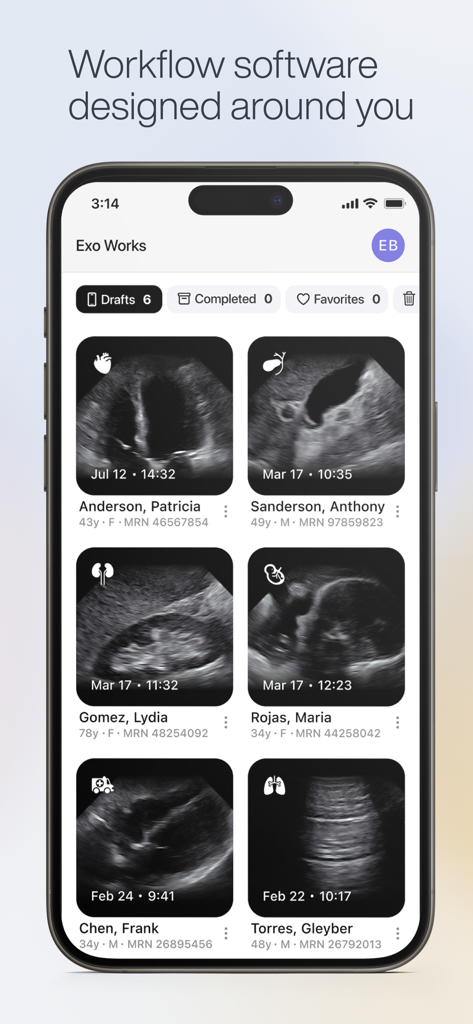

Exo Iris™ redefines the medical imaging ecosystem, blending high-performance proprietary silicon technology with real-time AI to deliver clinical answers when seconds count.